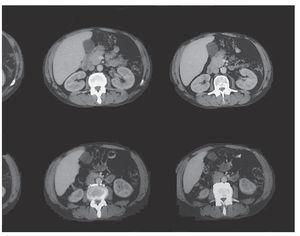

Se remitió al paciente al servicio de Urgencias hospitalario, desde donde ingresó en el servicio de Neumología con el diagnóstico de posible absceso pulmonar e insuficiencia respiratoria parcial; se inició tratamiento intravenoso con amoxicilina-clavulánico, gentamicina, broncodilatadores inhalados y esteroides a dosis de 60 mg diarios, con buena evolución clínica. Durante el ingreso se realizó tomografía computarizada (TC) de tórax, con el siguiente resultado: en el lóbulo inferior derecho se apreciaba área de infiltrado pulmonar con dos cavidades que presentaban nivel hidroaéreo en su interior, que podrían corresponder a proceso neoplásico y/o absceso pulmonar. En el medias-tino se apreciaban algunas adenopatías que alcanzaban algún centímetro de diámetro, en especial paratraqueales derechas, precarinales y subcarinales, que podían corresponder a cambios inflamatorios. Enfisema bulloso de tipo paraseptal que predominaba en los lóbulos superiores (fig. 1).

Figura 1. Tomografía computarizada: infiltrado pulmonar con cavidades en su interior.